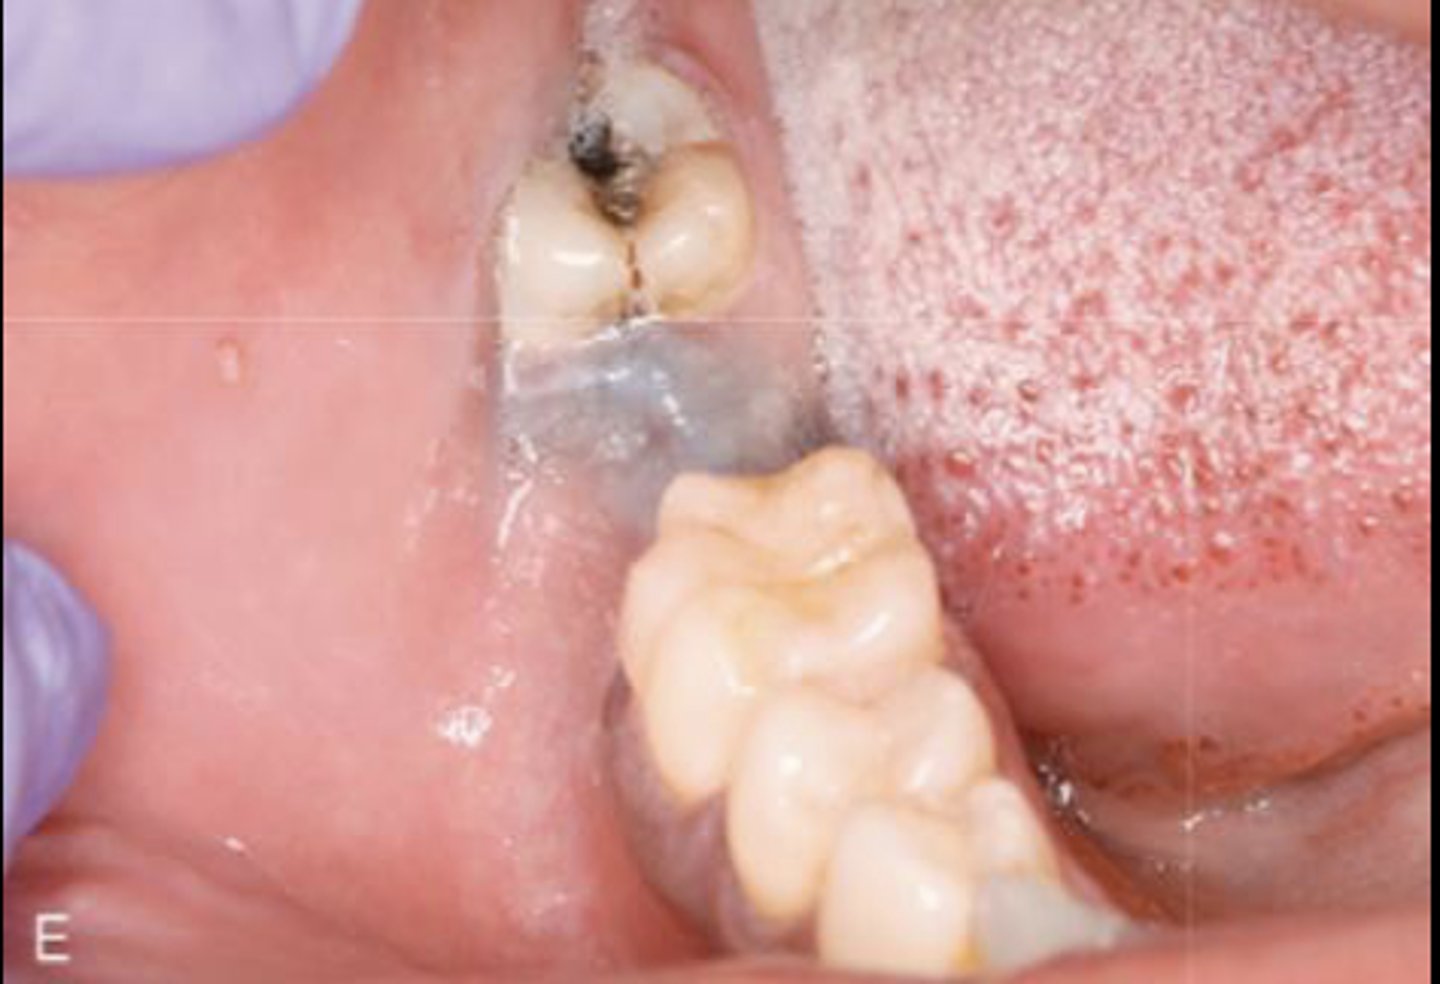

What type of pigmented lesion?

amalgam tattoo

These are clinical features of what?

- Asymptomatic, localized

- Blue-gray macule

- Localized around areas with amalgam restorations

amalgam tattoos

What is the most common location of amalgam tattoos?

gingiva/alveolar ridge mucosa (50%, then buccal mucosa, then floor of mouth)